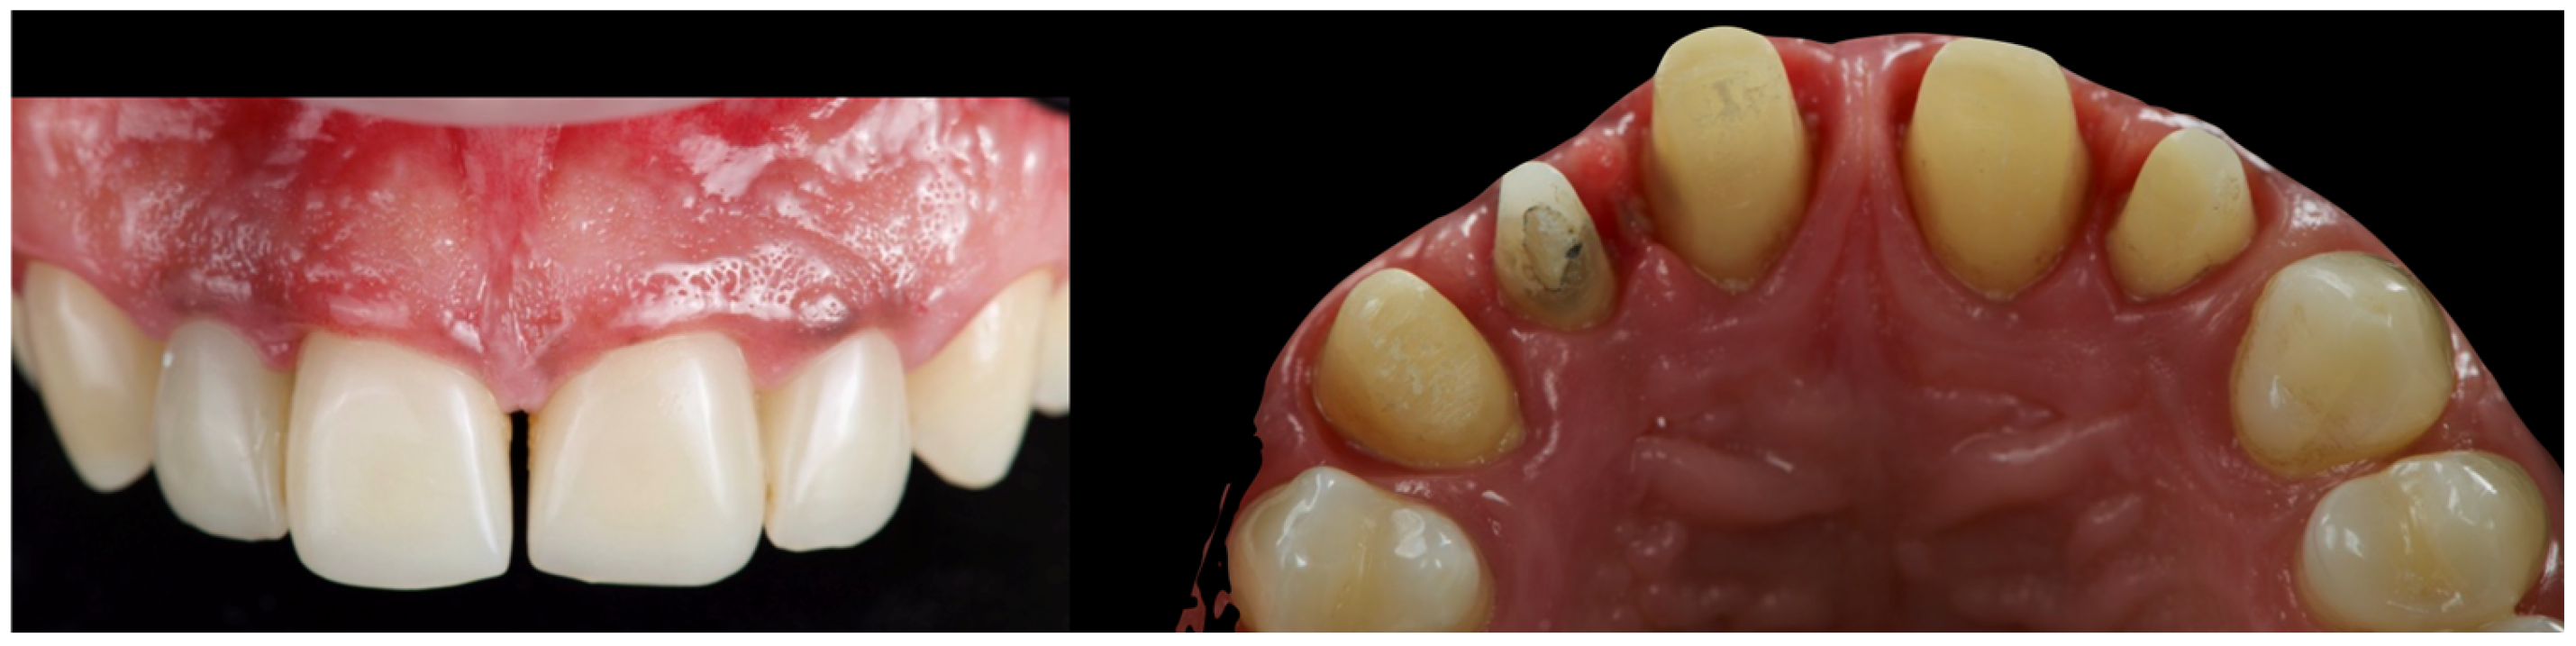

The first set of provisional restorations (Figure 10) was cemented using a non-eugenol temporary luting agent (Temp-Bond™ Clear, Kerr Dental, 8302 Kloten, Switzerland).

Figure 10. First provisional restoration.

These provisionals were segmented into two units (right and left) and maintained the existing interincisal diastema. The deep overbite was corrected, and an appropriate incisal guide was established. Both provisional restorations were progressively modified every 2–3 weeks to promote soft tissue adaptation, manage the emergence profile, and support the re-establishment of a new prosthetic cementoenamel junction (CEJ) over time. This approach also allowed for the continuous evaluation of the patient’s phonetics and functional dynamics. Approximately four months later, the preparations were refined under 16× magnification to optimise the emergence profiles and support soft tissue conditioning while preserving the edgeless finish line to enhance papillary stability and control (Figure 11).

The second provisional restorations (Figure 12) were luted using zinc phosphate cement (Harvard) and mixed with petroleum jelly to facilitate later removal. At this stage, the interincisal diastema was closed. During the second provisional phase, tooth 1.2 developed symptoms of thermal sensitivity and mild pain, necessitating endodontic treatment.

Figure 12. Second provisional restoration.